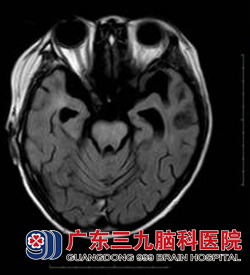

16岁的小志于1年前开始出现头晕、口角歪斜、流口水、言语不清、行走不稳、智力下降等症状。在当地医院按“大脑发育不全、颅神经功能障碍”予以药物治疗,效果不佳,近一个月以来症状进行性加重,为求进一步治疗于11月来到广东三九脑科医院神经内二科求诊。头颅磁共振检查发现其双侧基底节区、放射冠区、双侧侧脑室前角旁及脑干多发异常信号影,考虑脱髓鞘性病变可能性大(见图一),入院行相关检查,排除中枢神经系统感染、肿瘤等疾病,结合临床症状初步诊断为多发性硬化,予以激素冲击治疗1个月后复查头颅磁共振见原右侧放射冠区、中脑及桥脑病变内异常强化影已消失,桥脑及左侧基底节区病变范围较前缩小(见图二),患者吞咽困难、饮水呛咳、走路不稳等症状得以缓解;语言流利,肢体活动良好。www.999brain.com

图二:治疗后